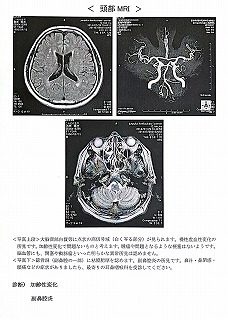

090 脳ドック

2024.18.14 荒尾市民病院 2023.08.10 荒尾市民病院

2024 PDF 2023 PDF

22.9.16 荒尾市民病院